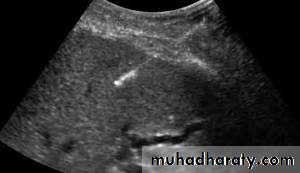

• US-guided biopsy of various body cavities and organs.

• Transvaginal US (TVUS): accurate assessment of gynecological problems and of early pregnancy up to about 12 weeks’ gestation